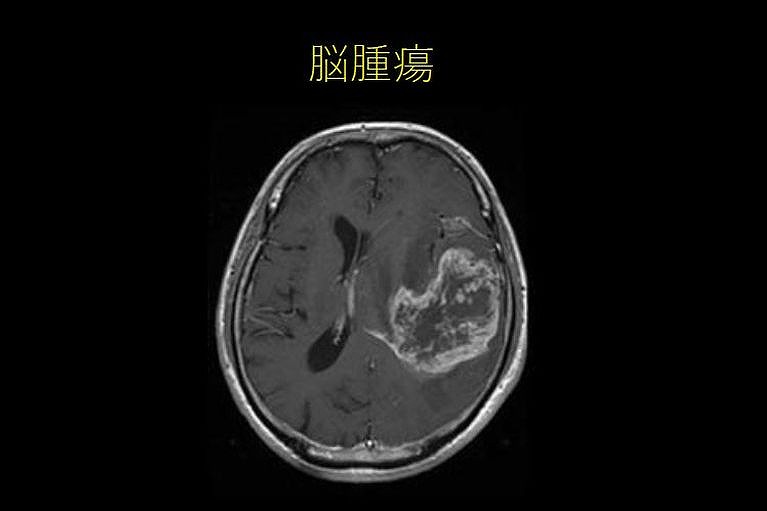

脳腫瘍

• 慢性進行性、早朝時頭痛脳腫瘍

• 吐き気のない突然の嘔吐

• けいれん発作、神経局所症状(言語障害、視野障害、運動障害など)